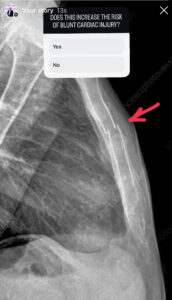

The Eastern Society for the Surgery of Trauma (11) in their approach to screening suspected BCI patients, did not consider isolated sternal fractures to predict BCI. They also proposed no further investigations in patients with a normal ECG and Troponin If all else was normal, the recommendation was for no monitoring of these patients.

This is where it becomes a little harder. There is a move away from working up isolated sternal fractures, however the evidence (some of which is presented below) is not robust. Due to this reason, my approach is to perform an ECG and high sensitivity troponin on patients with suspected BCI due to mechanism and clinical presentation. These are simple and inexpensive tests that can give us a lot of information. They aren’t perfect however and can be associated with false positives and negatives.

When should we investigate the patient with suspected blunt cardiac injury (BCI) and how do we work them up?